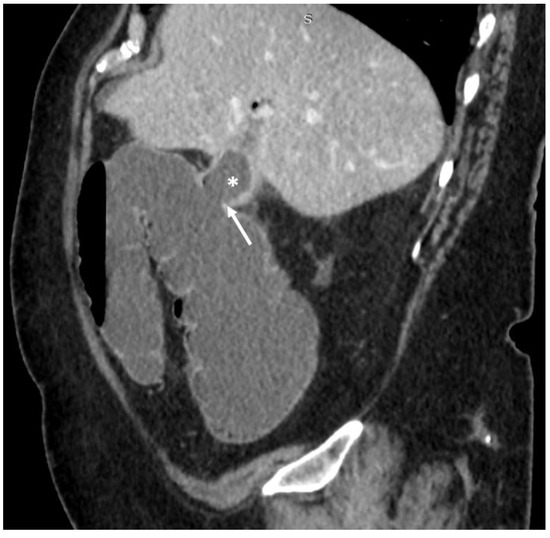

2. Case Presentation